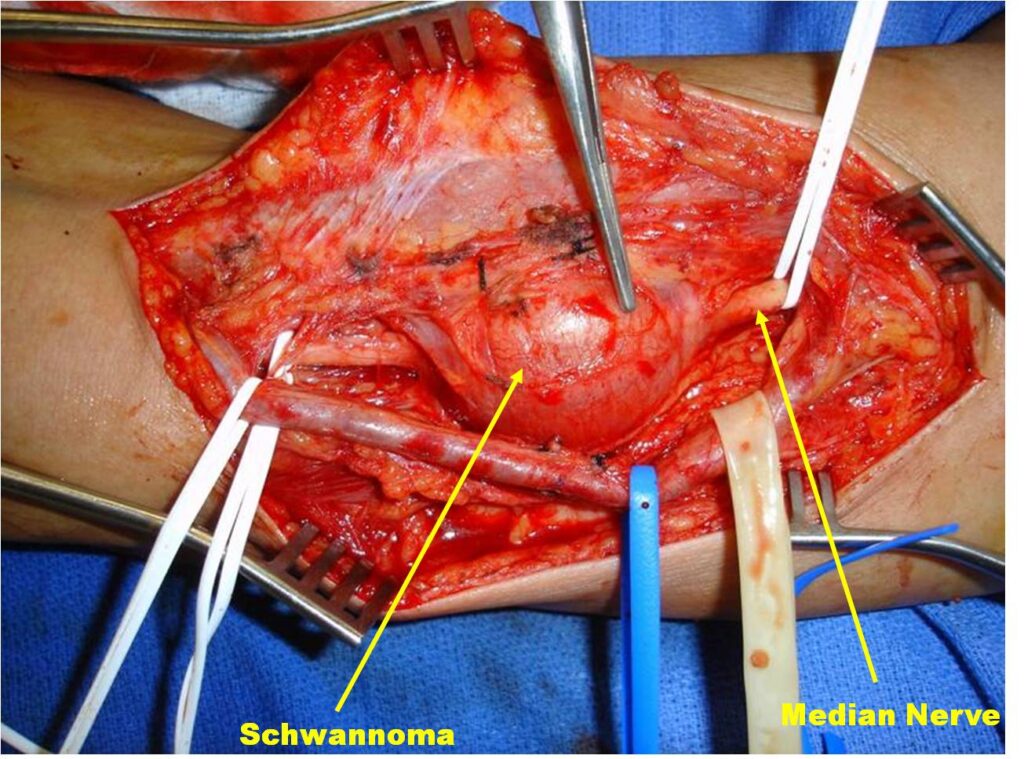

Treatment

• Surgical Excision (Fig. 9, 10, 11)

o Marginal Excision; Spare nerve from excision

The epineurium is opened carefully on a side opposite nerve fascicles and the mass is gently separated from the nerve fascicles and epineurium.

o Rarely if ever recurs

Fig. 9-11 Intraoperative photographs demonstrate medial approach to the arm and neurovascular dissection, including; median nerve and brachial artery. Schwannoma is easily distinguished in the median nerve. The sheath of the nerve is opened on the opposite side of the splayed out nerve fascicles and the tumor removed. The nerve was spared.